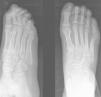

Caso clínico. Paciente de 13 años de sexo femenino que acudió a urgencias y refirió dolor difuso en el pie derecho sin ningún antecedente traumático previo. El dolor presentaba características mecánicas, aumentaba con la deambulación y disminuía con el reposo. Se realizó un estudio radiográfico inicial del pie con proyecciones dorsoplantar y oblicua sin apreciar ninguna lesión aparente (fig. 1), por lo que se recomendó a la paciente reposo y tratamiento con antiinflamatorios.

Transcurridos 10 días, la paciente acudió de nuevo a urgencias por persistencia del dolor en dicho pie. En esta ocasión, el dolor se localizó en el borde externo del pie sobre la diáfisis del quinto metatarsiano, por lo que se realizaron unas nuevas radiografías. En esta ocasión se detectó una imagen de reacción perióstica sobre la cortical externa de la diáfisis del quinto metatarsiano que se interpretó como una fractura por sobrecarga (fig. 1). Con este diagnóstico se le aplicó un vendaje enyesado y se envió para revisión a las 3 semanas.

Transcurrido este período se le retiró la inmovilización y se le autorizó la carga progresiva con plantillas, y se la citó para un nuevo control clínico y radiográfico en un mes. Cuando acudió a la revisión, la paciente se encontraba asintomática. Sin embargo, presentaba una tumoración de 2×2cm de diámetro levemente eritematosa, no fluctuante ni dolorosa a la palpación y adherida a planos profundos localizada en el borde externo del pie sobre el quinto metatarsiano. Radiográficamente, se apreció una tumoración excéntrica, ovalada, polilobulada, de aspecto lítico, por debajo del periostio de la cortical lateral de la diáfisis del quinto metatarsiano (fig. 1) y sin lesión de la cortical ni de la zona medular. También observamos un despegamiento del periostio de la cortical medial. Ante estos hallazgos se decidió su ingreso hospitalario para estudio y tratamiento.